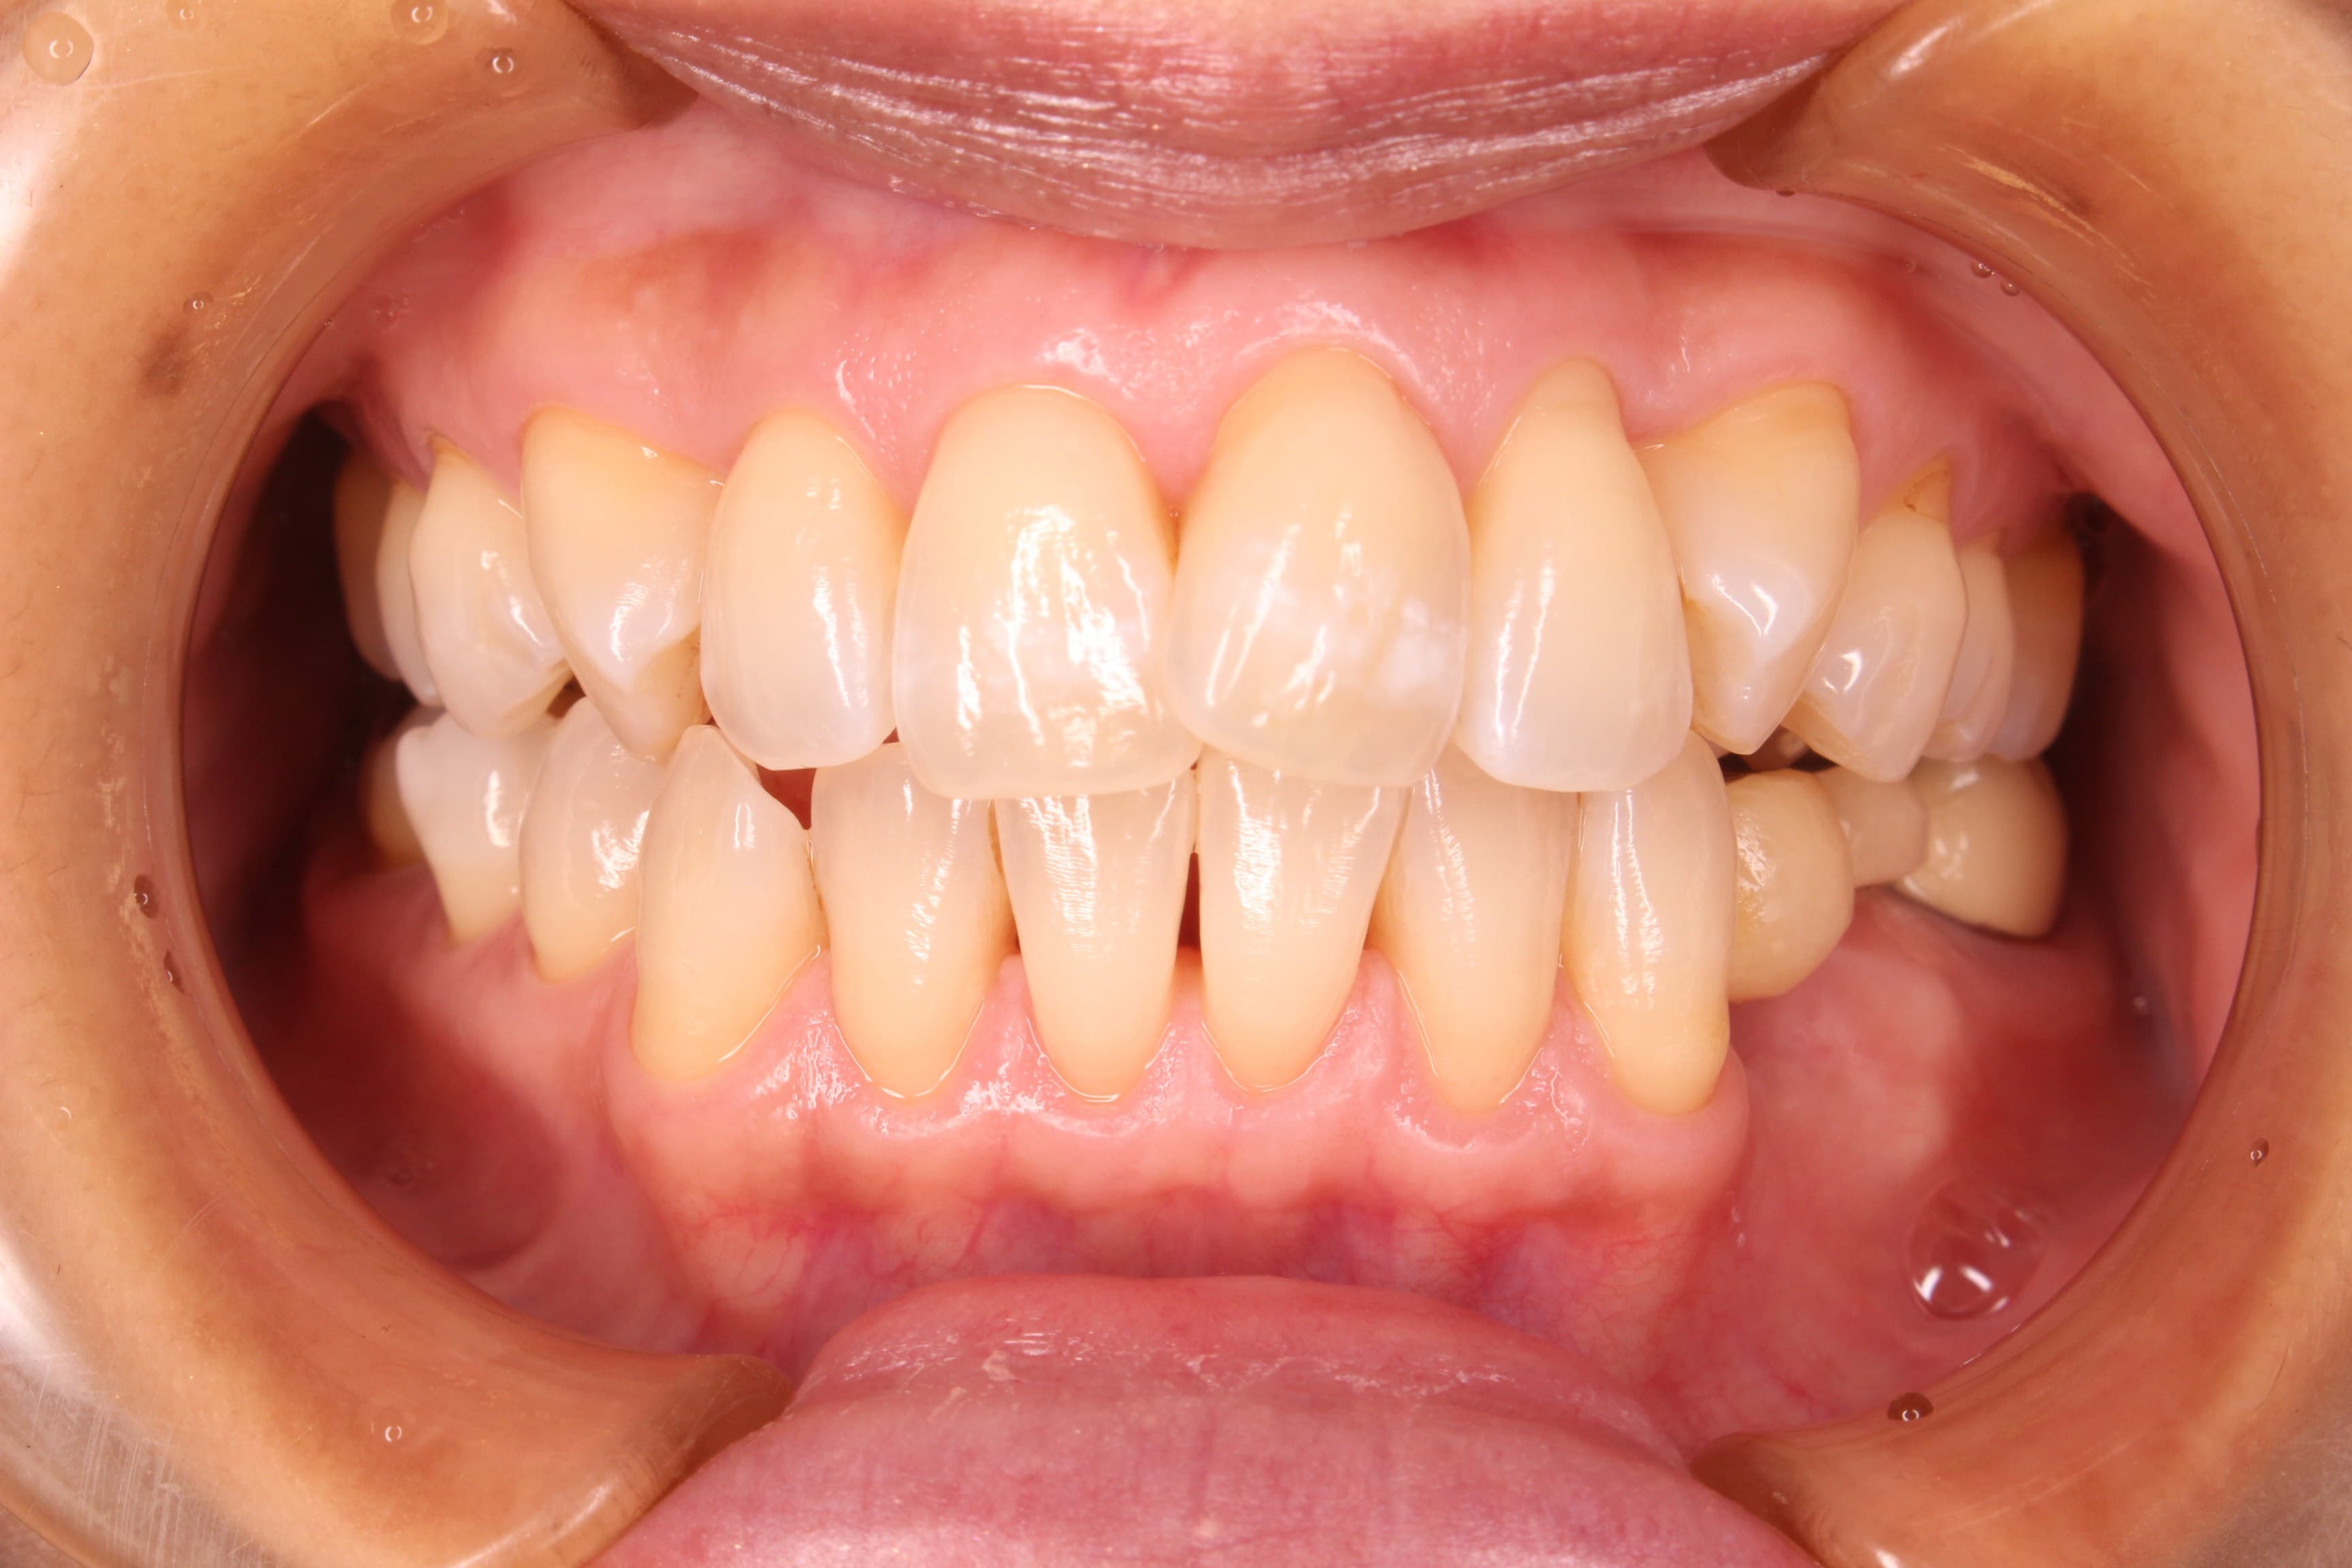

既に口腔ケアに対する意識が高かったこともあり、とても綺麗にお手入れをしていただくことができました。

そして要所を理解して忙しい日常でもうまくコントロールして継続していただけている為、非常にきれいな状態になったと思います。

※これからインプラント治療を行う予定です。